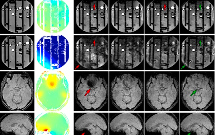

L'IA accélère l'acquisition des données des IRM